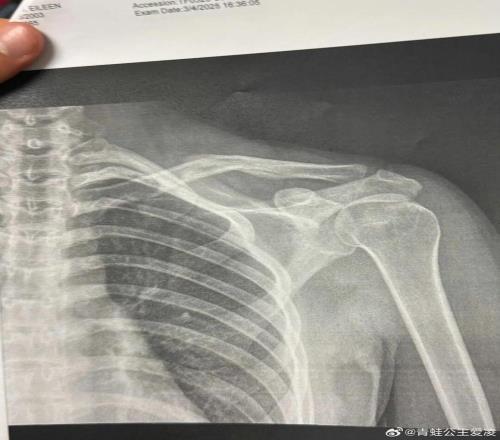

2025年是谷愛凌口中“職業(yè)生涯最艱難的一年”,三月她在阿斯本訓練中遭遇嚴重的腦震蕩,導致急性顱內(nèi)出血、癲癇發(fā)作,一度失去意識五分鐘,如此嚴重的傷病讓她一度認為自己再也醒不過來。八月的意外受傷讓她錯過了亞冬會,十一月復出后的失利又引發(fā)外界的質(zhì)疑,種種猜測都讓她的心理得到深刻的錘煉。